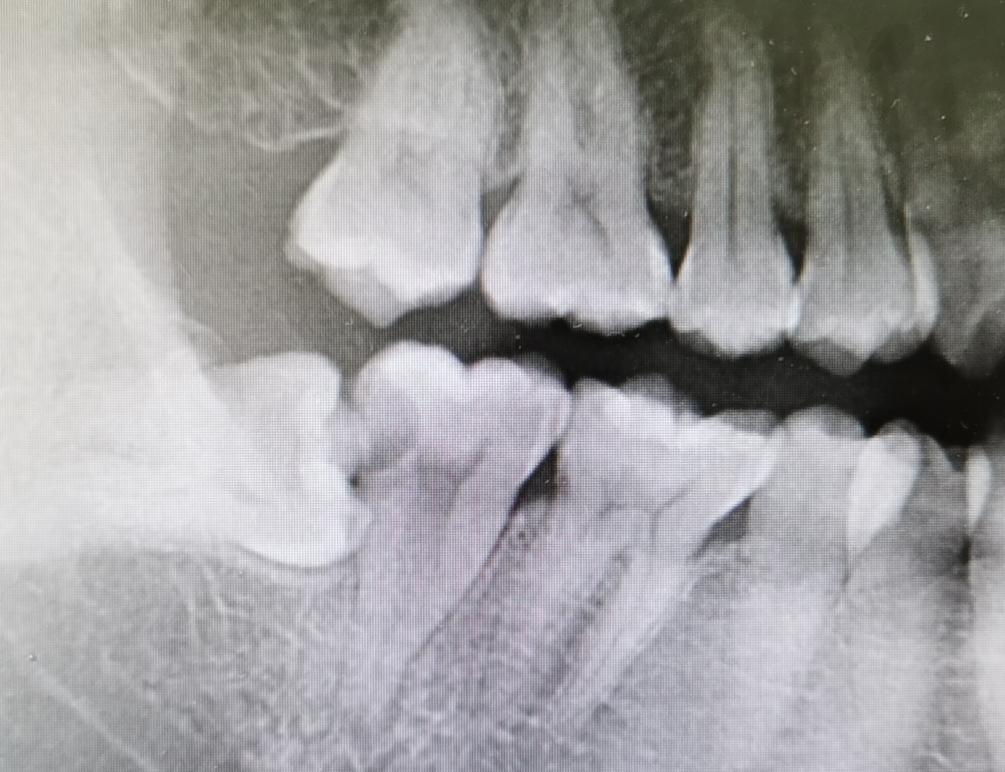

初步考虑患者为47慢性牙髓炎后,我为明确诊断,建议患者进行了x线片检查,检查结果提示:冠部低密度影近髓腔,根管内无填充物影,根尖区无低密度影。

经过治疗后,患者定期来我门诊进行了复诊,诉未再出现牙齿疼痛,无其他不适,我再次对患者进行了口腔检查:47暂封物在,无叩痛。于是再次对患者进行治疗:去除上次治疗时髓腔内封药,3%Naclo冲洗,然后预备根管,超声荡洗,使用iRoot sp+热牙胶垂直加压填充,拍x线提示恰填,上邻面修复系统,3M Single Bond Universal+流动树脂+3M Filtek P60树脂填充,调和抛光,择日再行冠修复。